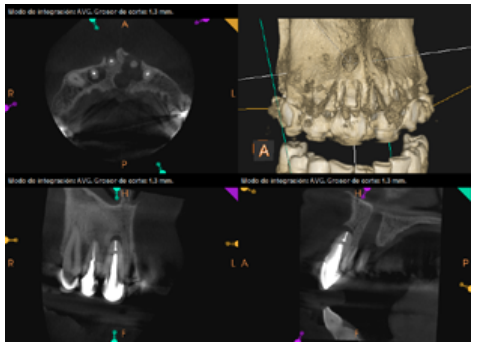

To confirm the endodontic origin and the size of the lesions, tomographic examinations were performed with a slice thickness of 75 microns using CBCT CS8100 (Carestream Dental™), in which radiolucent periapical lesions were observed at the level of 12, 11, 21 (with bicortical involvement), 25 and vestibular roots at 26 (Figures 4 to 8).

After the microsurgery was performed on 25, the patient had no symptoms and the control tomographies at 12 months (in 25) and at 18 months in the remaining teeth showed regeneration of pre-existing radiolucent periapical lesions on all treated teeth (Figures 13 to 16).